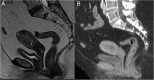

Endometrial cancer is the most common gynaecologic malignancy in developed countries and its incidence is increasing. First-level treatment, if no contraindicated, is based on surgery. Pre-operative imaging is needed for evaluation of local extent and detection of distant metastases in order to guide treatment planning. Radiological evaluation, based on transvaginal ultrasound, MR and CT, can make the difference in disease management, paying special attention to assessment of entity of myometrial invasion, cervical stromal extension, and assessment of lymph nodal involvement and distant metastases.